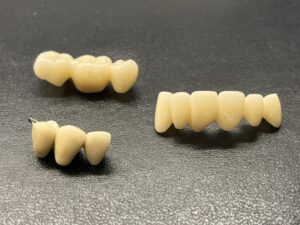

こちらはこれから実際にセット予定の色々な種類のセラミックです。

セラミックによる修復治療は当院の専門分野です。

一般的な修復治療よりも緻密な型取りと、信頼できる技工所との連携による「精密修復」をご提供します。

セラミックの材料にもいくつか種類があり、

それぞれ特徴があるため患者様のケースにあったものをチョイスしています。

こちらが実際のセット後の写真です。

上の犬歯から犬歯までの6本の歯に審美治療を行っています。

治療のタイミングが異なるため

メタルセラミック、レイヤリングジルコニア、

ジルコニアラミネートべニア(付け爪のように薄いジルコニアを張り付ける方法)

等の材料をつかっています。

スーパーセラミスト常泉氏(ホームページ参照)が丹念に製作しております。

自然で美しい仕上がりに満足いただけています。